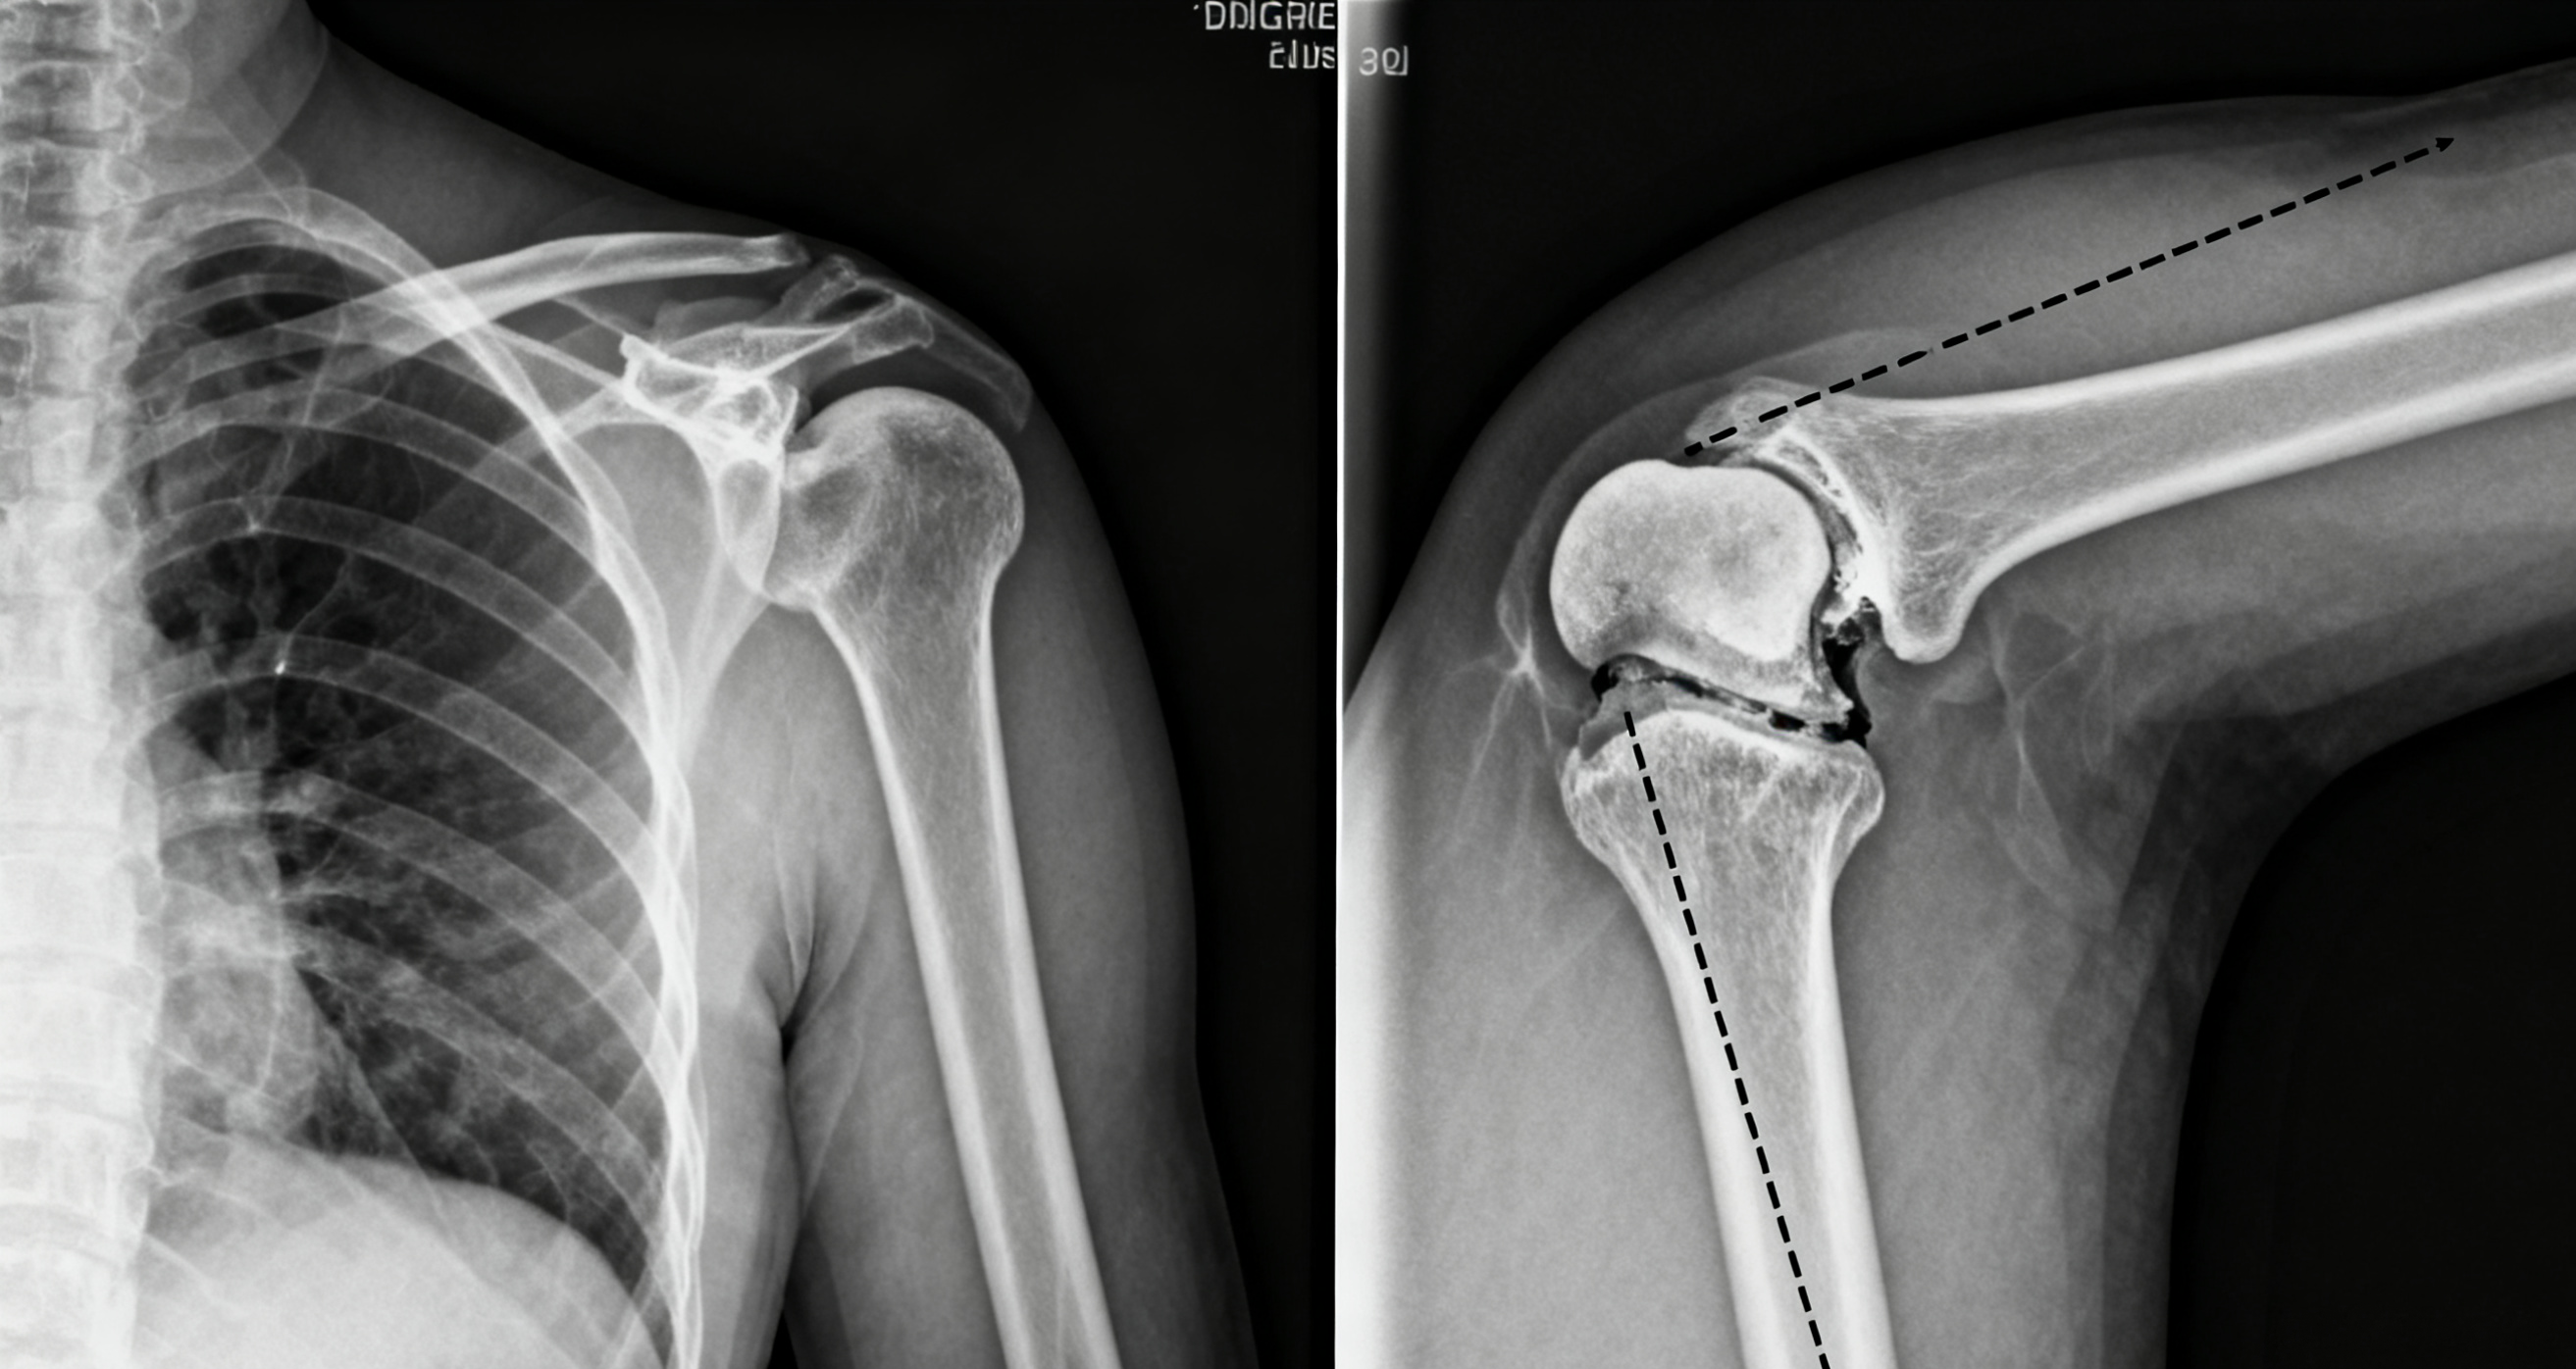

1. X线检查:首选基础检查,需拍摄肩关节正位片+腋位片(或穿胸位片)。

典型X线表现:“肱骨头不在关节盂内”,前脱位常伴“泪滴征”(关节囊内出血导致的弧形阴影),复杂性脱位可见骨折线。